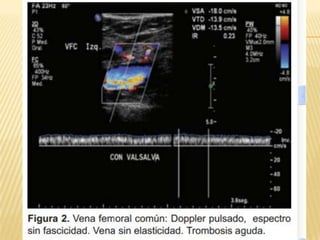

EVOLUCIÓN ECOGRÁFICA DE LA TROMBOSIS

VENOSA PROFUNDA EN PACIENTES CON

TROMBÓLISIS FARMACOLÓGICA

   Centro Médico ABC. The American British

Cowdray Medical Center IAP

   Anales de Radiología México 2010;2:76-

79. artíCulo original. Dr. José de Jesús

Rosas Sánchez, Dr. Miguel Ángel Ríos

Nava.